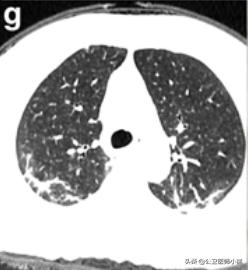

肺部好转

如果患者得到有效的治疗,或者患者症状较轻免疫力成功抵抗了病毒,炎症将进一步吸收程度开始降低。

开始恢复的肺